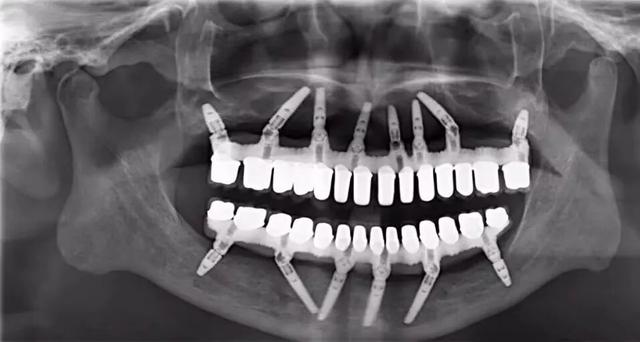

即刻种植牙听起来很神奇,但它的操作是有迹可循的。传统种植牙一般在拔牙后的2-3个月才开始种牙,而即刻种植牙可以在患者拔完牙后,立即在窝孔中植入人工牙根。因为不需要等待几个月的拔牙创伤修复时间,也避免了重新钻孔的问题,大大缩短了种牙的疗程时间。

即刻种植牙并非是这两年才兴起的「黑科技」医疗,它跟传统种植牙一样,是一项已经成熟的医疗技术。